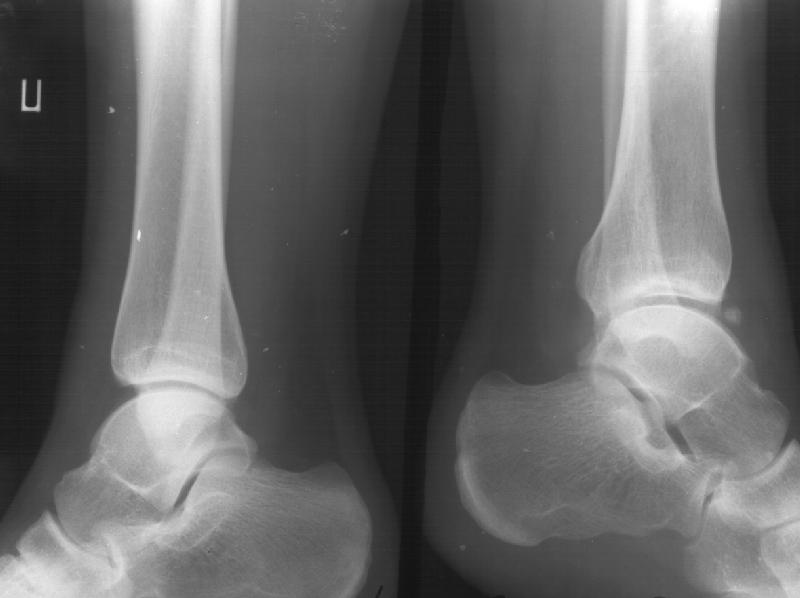

Девочка 14 лет полтора года назад оперирована в детской больнице по поводу спирального перелома костей голени (снимок 1)- выполнен закрытый остеосинтез стержнем Богданова, введенным ретроградно с медиальной стороны (снимок 2). Фиксатор после сращения удален

(см. снимки 3 и 4, после удаления, для сравнения со здоровой стороной, фас - стоя с нагрузкой на обе ноги). В настоящее время беспокоят боль и отеки в области голеностопного сустава при нагрузках, после ходьбы. В покое и ночью боли нет.Амплитуда движений в голеностопном суставе практически полная. Имеется заметная боковая нестабильность, т.е. несостоятельность дельтовидной связки и межберцоого синдесмоза. Складывается впечатление, что при остеосинтезе был отколот и смещен в сторону сустава костный фрагмент позади внутренней лодыжки, увеличилось смещение отломка заднего края, что привело к столь ранним проявлениям деформирующего артроза. Встает вопрос - что делать сейчас?Артодез - наверно, рано. Ревизию сустава, моделирующую резекцию?Пластику связок? Что-то еще? Заранее спасибо.